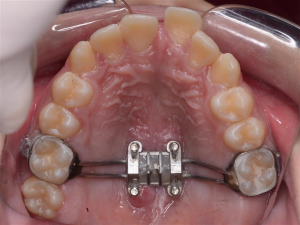

2. Dụng cụ nong rộng hàm cố định

Đây là khí cụ truyền thống được nhiều người lựa chọn vì đem lại hiệu quả nhanh, rút ngắn thời gian nong hàm. Tuy nhiên, khi sử dụng nong hàm cố định, khách hàng có thể cảm thấy khó chịu, vướng víu và khó vệ sinh răng miệng trong thời gian đầu.

Dụng cụ nong rộng hàm cố định